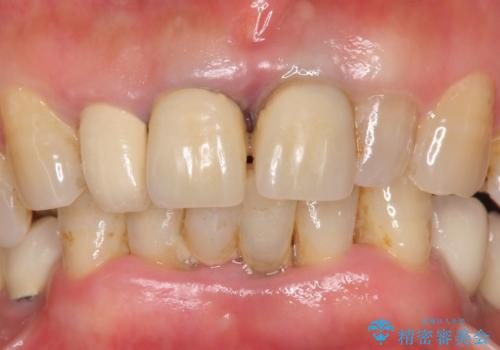

- 保険治療で装着されたかぶせ物と詰め物を変更したいとのことで来院されました。

自然なオールセラミックへ変更することとなりました。

金属を使わないセラミックへ変更することで、自然な見た目になるとともに、ぴったりとした精度の高いかぶせ物を装着することができました。